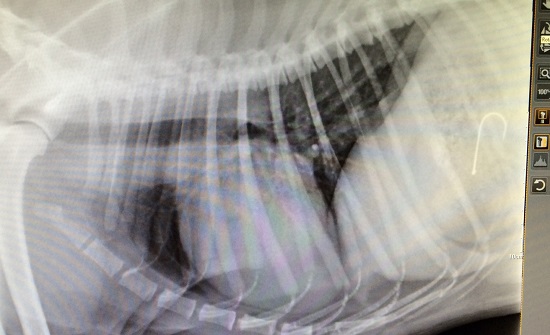

- Digital Radiography (X-ray)

Below - identification of a fish hook trapped in a dog’s stomach.